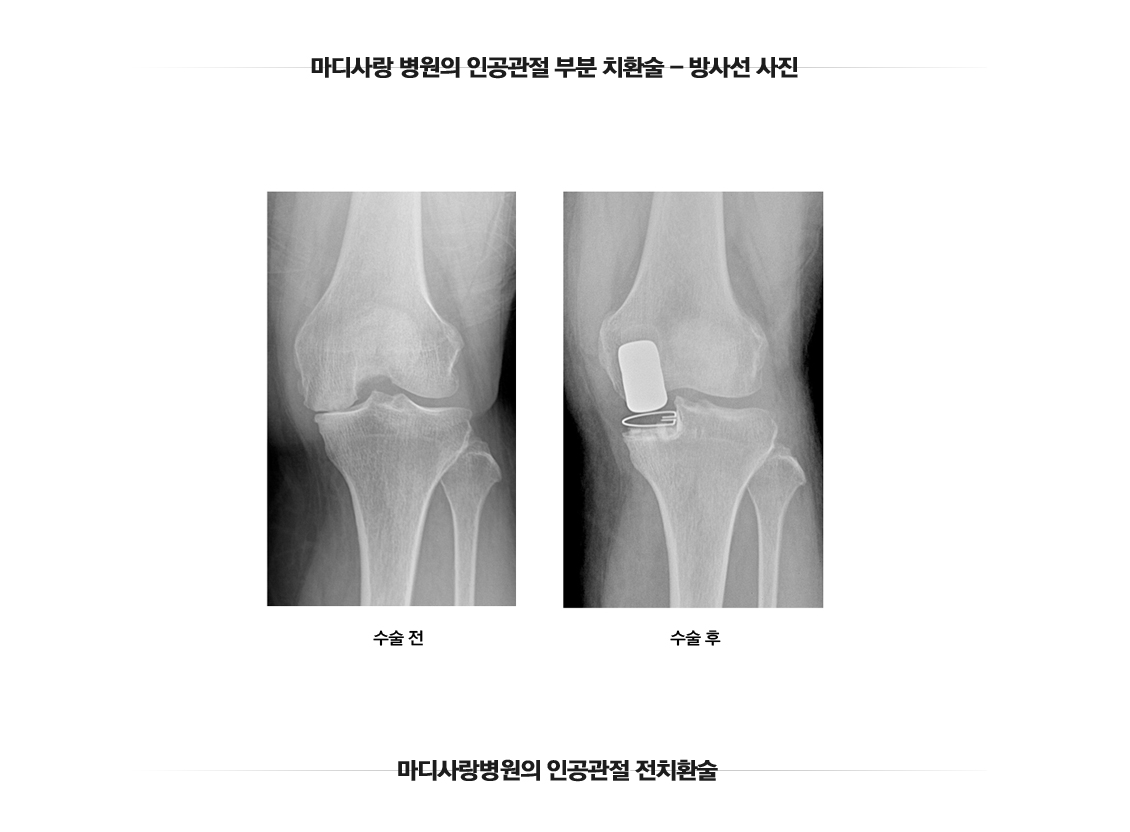

人工关节部分置换术

人工半膝关节置换术